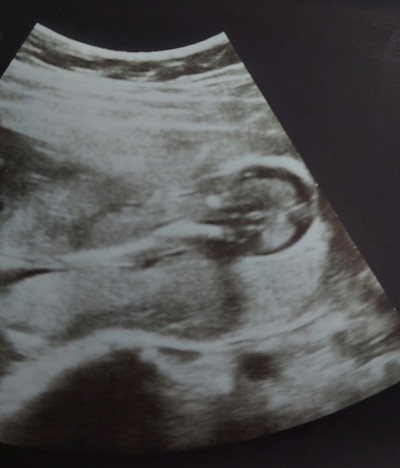

Bakar mısınız bu bebeğin cinsel organı mı acaba

image

Evet canım erkek gibi görünüyor hayırlısı bakalım<3

Pipi gibi görünüyor inşallah sağlıkla kucağınıza alırsınız

Erkek gibi yahminde bulunmadı mi

Bende bacak arasında birşey gördüm ama doktor o kemik de ne alaka ise kız dedi ama ben erkek gibi hissediyorum ayrıntılı ultrasonu bekliyorum net olsun diye

Ellerini yüzüne kapatmış gibi kıpırdarken cıkmış sanki

Yani ben pipi gibi bişey görüyorum sanki ana belki çocuğun kafasıdır doktorlar ayrıt edebiliyor

Bende pipi gibi görüyorum ama net değil kemiğede benziyor pipi görününce alttaki yumurta sınında görünmesi gerekiyor benim öyle pipi ve yumurtası görünüyor du

Kız bu bebek hayırlı olsun